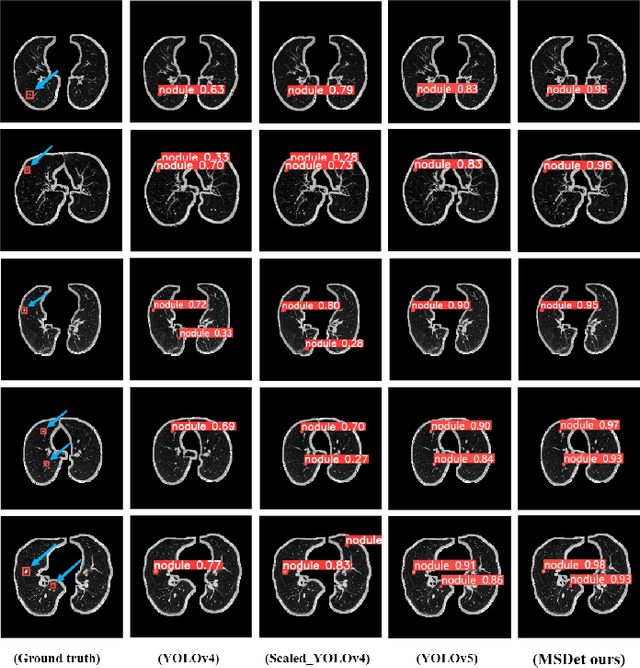

Abstract:Pulmonary nodules are critical indicators for the early diagnosis of lung cancer, making their detection essential for timely treatment. However, traditional CT imaging methods suffered from cumbersome procedures, low detection rates, and poor localization accuracy. The subtle differences between pulmonary nodules and surrounding tissues in complex lung CT images, combined with repeated downsampling in feature extraction networks, often lead to missed or false detections of small nodules. Existing methods such as FPN, with its fixed feature fusion and limited receptive field, struggle to effectively overcome these issues. To address these challenges, our paper proposed three key contributions: Firstly, we proposed MSDet, a multiscale attention and receptive field network for detecting tiny pulmonary nodules. Secondly, we proposed the extended receptive domain (ERD) strategy to capture richer contextual information and reduce false positives caused by nodule occlusion. We also proposed the position channel attention mechanism (PCAM) to optimize feature learning and reduce multiscale detection errors, and designed the tiny object detection block (TODB) to enhance the detection of tiny nodules. Lastly, we conducted thorough experiments on the public LUNA16 dataset, achieving state-of-the-art performance, with an mAP improvement of 8.8% over the previous state-of-the-art method YOLOv8. These advancements significantly boosted detection accuracy and reliability, providing a more effective solution for early lung cancer diagnosis. The code will be available at https://github.com/CaiGuoHui123/MSDet